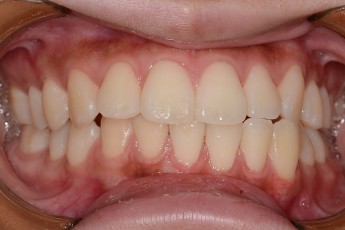

Before & After

Before

After